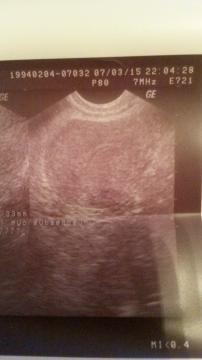

Pro větší náhled klikněte na obrázek

Dobry den. Tento tyzden som absolvovala gynekologicke vysetrenie v privatnej gynekologicked ambulancii v UK, koli problemovej menstruacii. Sonograficke vysetrenie ukazalo ze mam zvatsenu maternicu o 7cm v tvare haciku (vid sono v prilohe). Vysetrenie ukazalo aj neobvikly tvar krcka maternice. Mam 20 rokov a antikoncepciu (logynol) pouzivam 6 rokov kvoli menstruacii, pretoze ak by som ju nebrala menstruaciu by som vobec nedostala. V strede menstruacie mam silne pichave bolesti a s bolestami mam vzdy aj silnejsie krvacanie. Po konzultacii som mala predpisanu druhu antikoncepciu cerrelle a mala som spraveny krvny rozbor ktory ukazal znizene hodnoty INR (0.8) a APTT (23). Chcela by som sa opytat ci tieto hodnoty su v norme a popripade dalsi postup. Dakujem za kazdu radu a prajem pekny den.

Dobrý den, hodnota INR 0,8 je ještě v normě (spodní hranice), aPTT 23s je již snížená hodnota, která bývá snížená při poraněních a zánětech (myslím si, že pokud byl odběr prováděn v době menstruace či krátce po ní, může být hodnota ovlivněna tím). Obě dvě hodnoty, pokud jsou snížené, mohou ukazovat na poruchu koagulačního systému, ve smyslu hyperkoagulačního stavu.Vaše obtíže budou mít spíše příčinu ve zvětšené děloze, kterou by bylo potřeba objasnit důkladnějším vyšetřením - CT, MR nebo hysteroskopie s odebráním vzorku tkáně.